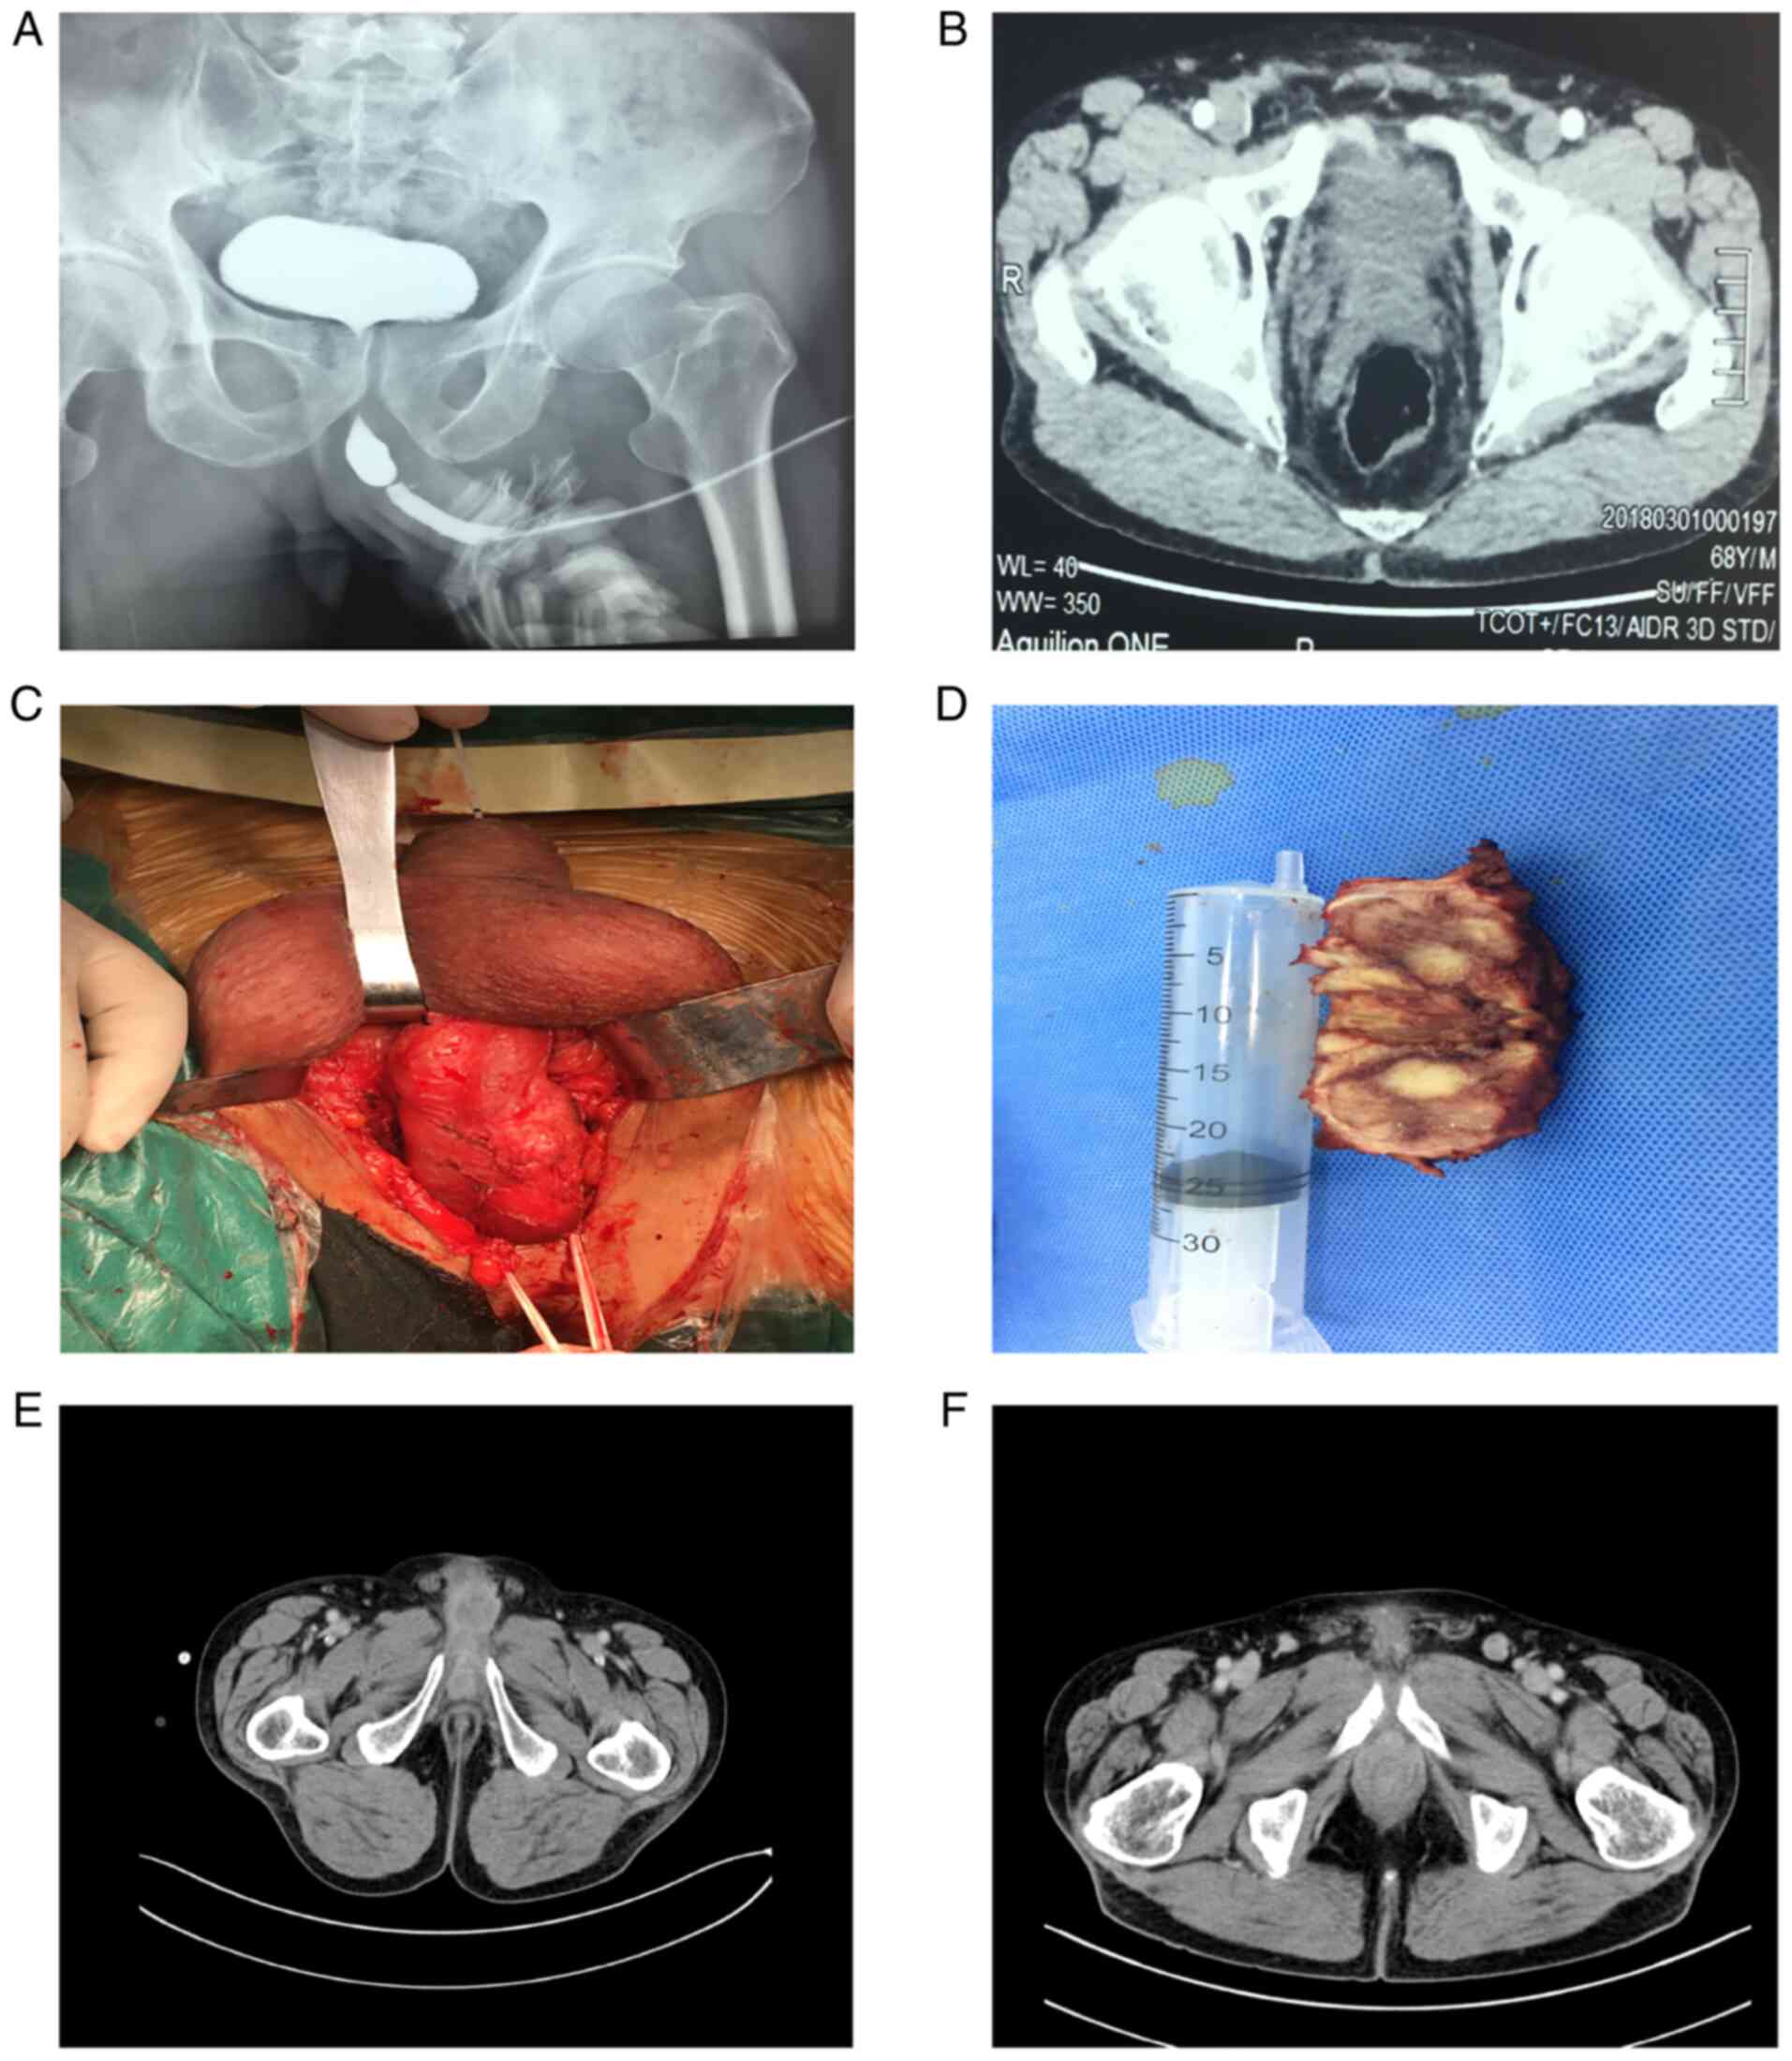

The patient had undergone several imaging examinations. Urethrography indicated an apparent urethral stricture (Fig. 1A). Abdominal computed tomography (CT; Fig. 1B) demonstrated the presence of a neoplastic lesion in the overhanging part of the penis, with approximate dimensions of 4.0x2.0x2.0 cm. Concomitantly, abdominal CT indicated that the inner wall of the bladder was smooth in the absence of an apparent space-occupying sign. The bladder was devoid of inguinal nodules, and organ or other nodal metastases (cT3 cN0 cM0). Preoperative urethral cystoscopy confirmed the presence of urethral stricture and the space-occupying site was located approximately at a site 7.0 cm from the external orifice of the urethra. After the replacement of a thinner pediatric ureteroscope, it was still unable to pass through the narrow segment. Therefore, a fine needle biopsy had to be performed on the mass site of the patient. The results suggested that the tumor was malignant. Subsequently, a partial penectomy was performed. Notably, during the surgery, it was found that the mass had invaded the corpus cavernosum (Fig. 1C and D).

Figure 1

Imaging examination and gross specimens of urethral tumors. (A) Retrograde urethrogram demonstrated urethral strictures of the bulbar urethra and the uneven wall of the urethra. (B) A lower abdominal CT examination indicated that the tumor was located in the urinary bulb and its dimensions were approximately 4.0x2.0x2.0 cm. The tumor indicated apparent inhomogeneous enhancement. (C) Partial penectomy of the urethral tumor. (D) The mass following partial penectomy. (E) Re-examination of abdominal enhancement CT demonstrated uneven enhancement of the anterior part of the corpus cavernosum of the penis. (F) Enlarged left inguinal lymph nodes with apparent enhancement. CT, computed tomography.

Therefore, the patient was discharged. During the 3-month postoperative follow-up, no apparent abnormality was noted according to the laboratory or imaging examination. However, 9 months later, the patient returned to the hospital due to recurrent dysuria with hematuria and a re-examination of abdominal enhancement CT indicated that the enhancement of the anterior part of the cavernous body was decreased (Fig. 1E), the enhancement of the prostate was uneven, and the bilateral inguinal lymph nodes were enlarged with apparent enhancement (Fig. 1F). The final clinical diagnosis was tumor recurrence with prostate invasion and bilateral inguinal lymph node metastasis. Due to the poor medical condition of the patient, multimodal treatment was declined, including salvage surgery and/or chemoradiotherapy, and cystostomy was accepted to merely relieve urinary retention. As a consequence of his progressive disease, the condition of the patient significantly deteriorated. The patient succumbed to his illness, 3 months after the recurrent presentation.